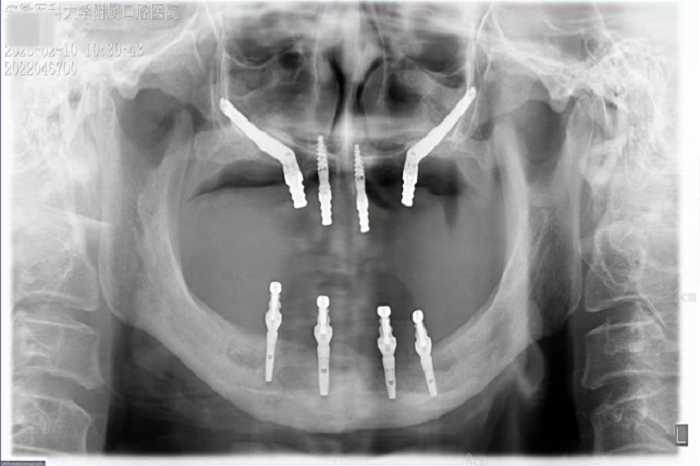

2月8日,街射 种植科主任刘鑫带领其团队完成一例上颌骨“穿颧”、下颌神经游离种植手术。该手术是继2019年种植科完成首例穿颧种植术后的第二例穿颧种植。

据悉,患者潘女士54岁,由于重度牙周炎导致全口牙齿缺失,严重影响面容及咀嚼功能,因颌骨严重萎缩无法进行活动义齿修复,遂来街射 种植科要求行上颌稳固的修复。通过检查发现潘女士上下颌骨骨量严重不足,经反复比对和考量,刘鑫主任制定了对患者上颌骨进行穿颧种植修复、下颌骨通过神经游离进行种植的方案。经过患者与家属深思熟虑后,接受了行穿颧种植术的建议。治疗组通过专业三维设计软件规划植体,口腔颌面外科和种植科专家共同完成了穿颧种植手术。患者术后第一天情况良好,无明显肿胀,精神状态佳。